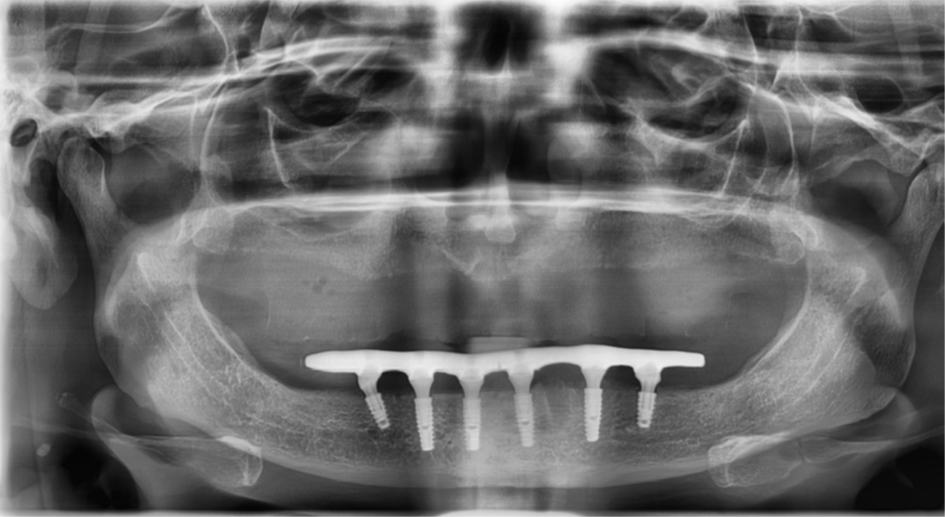

Figura 3 – Raio-X panorâmico inicial sem próteses removíveis em boca.

Figura 15 – Raio-X panorâmico pós-operatório com os seis implantes posicionados e os mini-cônicos instalados.